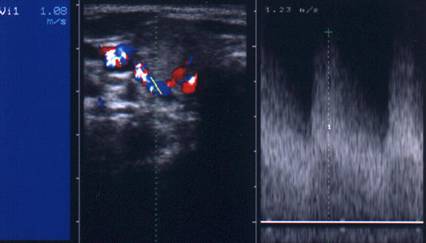

Aceeasi pacienta. Vascularizatie intensa periferica si in interiorul nodulului.

Aceeasi pacienta. Velocitate ridicata a picului sistolic arterial (1,08 m/s').

AdenomUL Plummer